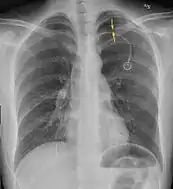

Chest X-ray

A plain chest radiograph, ideally with the X-ray beams being projected from the back (posteroanterior, or "PA"), and during maximal inspiration (holding one's breath), is the most appropriate first investigation.[30] It is not believed that routinely taking images during expiration would confer any benefit.[31] Still, they may be useful in the detection of a pneumothorax when clinical suspicion is high but yet an inspiratory radiograph appears normal.[32] Also, if the PA X-ray does not show a pneumothorax but there is a strong suspicion of one, lateral X-rays (with beams projecting from the side) may be performed, but this is not routine practice.[15][19]

Anteroposterior inspired X-ray, showing subtle left-sided pneumothorax caused by port insertion

Lateral inspired X-ray at the same time, more clearly showing the pneumothorax posteriorly in this case

Anteroposterior expired X-ray at the same time, more clearly showing the pneumothorax in this case

It is not unusual for the mediastinum (the structure between the lungs that contains the heart, great blood vessels, and large airways) to be shifted away from the affected lung due to the pressure differences. This is not equivalent to a tension pneumothorax, which is determined mainly by the constellation of symptoms, hypoxia, and shock.[13]

The size of the pneumothorax (i.e. the volume of air in the pleural space) can be determined with a reasonable degree of accuracy by measuring the distance between the chest wall and the lung. This is relevant to treatment, as smaller pneumothoraces may be managed differently. An air rim of 2 cm means that the pneumothorax occupies about 50% of the hemithorax.[15] British professional guidelines have traditionally stated that the measurement should be performed at the level of the hilum (where blood vessels and airways enter the lung) with 2 cm as the cutoff,[15] while American guidelines state that the measurement should be done at the apex (top) of the lung with 3 cm differentiating between a "small" and a "large" pneumothorax.[33] The latter method may overestimate the size of a pneumothorax if it is located mainly at the apex, which is a common occurrence.[15] The various methods correlate poorly but are the best easily available ways of estimating pneumothorax size.[15][19] CT scanning (see below) can provide a more accurate determination of the size of the pneumothorax, but its routine use in this setting is not recommended.[33]

Not all pneumothoraces are uniform; some only form a pocket of air in a particular place in the chest.[15] Small amounts of fluid may be noted on the chest X-ray (hydropneumothorax); this may be blood (hemopneumothorax).[13] In some cases, the only significant abnormality may be the "deep sulcus sign", in which the normally small space between the chest wall and the diaphragm appears enlarged due to the abnormal presence of fluid.[16]